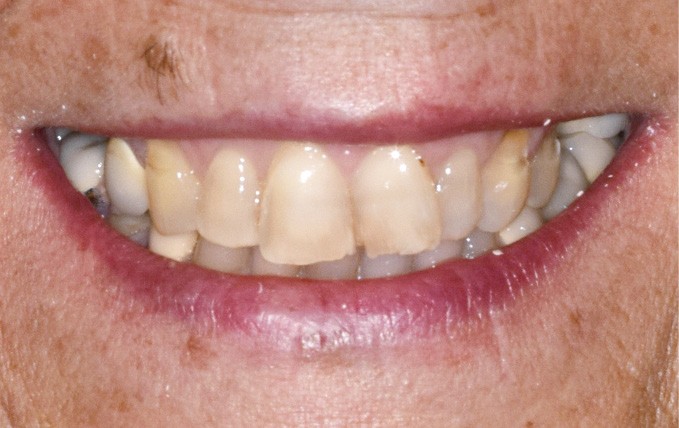

Une patiente d’une cinquantaine d’années consulte pour refaire sa prothèse amovible partielle métallique maxillaire, source d’inconfort (fig. 1 et 2).